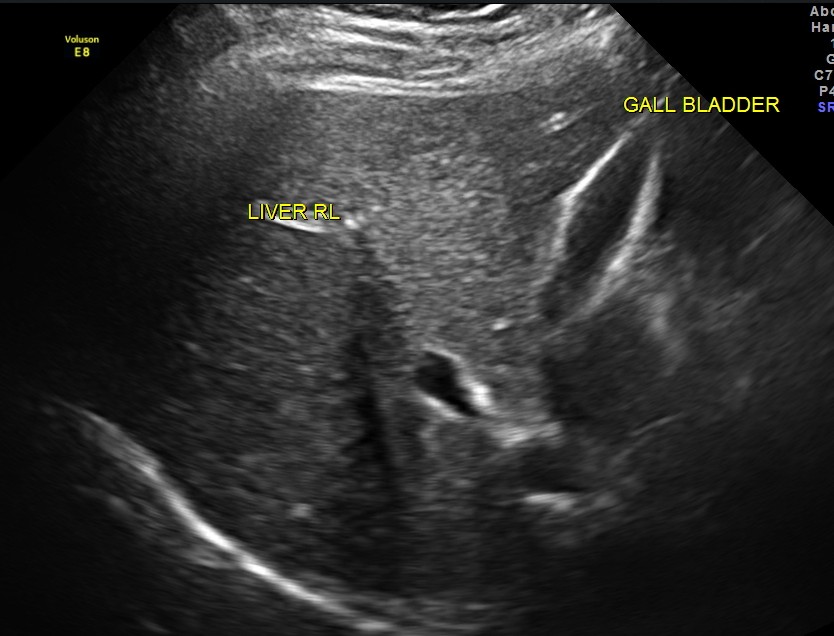

An ultrasound abdomen was done as part of evaluation of anemia.

Now for the unexpected findings . To finish off the scan , I was sweeping the aorta, IVC and the pre and post aortic regions.

The following image was obtained with the transducer in the mid epigastric region and an inch to the left of the mid line.

This mass visualised there . This was antero-lateral to the aorta and showed mixed echotexture , with some vascularity.

This was not mobile and all i could offer was a description of what was seen with the impression of a mass of unknown origin – ?? enlarged node and advised further work up.